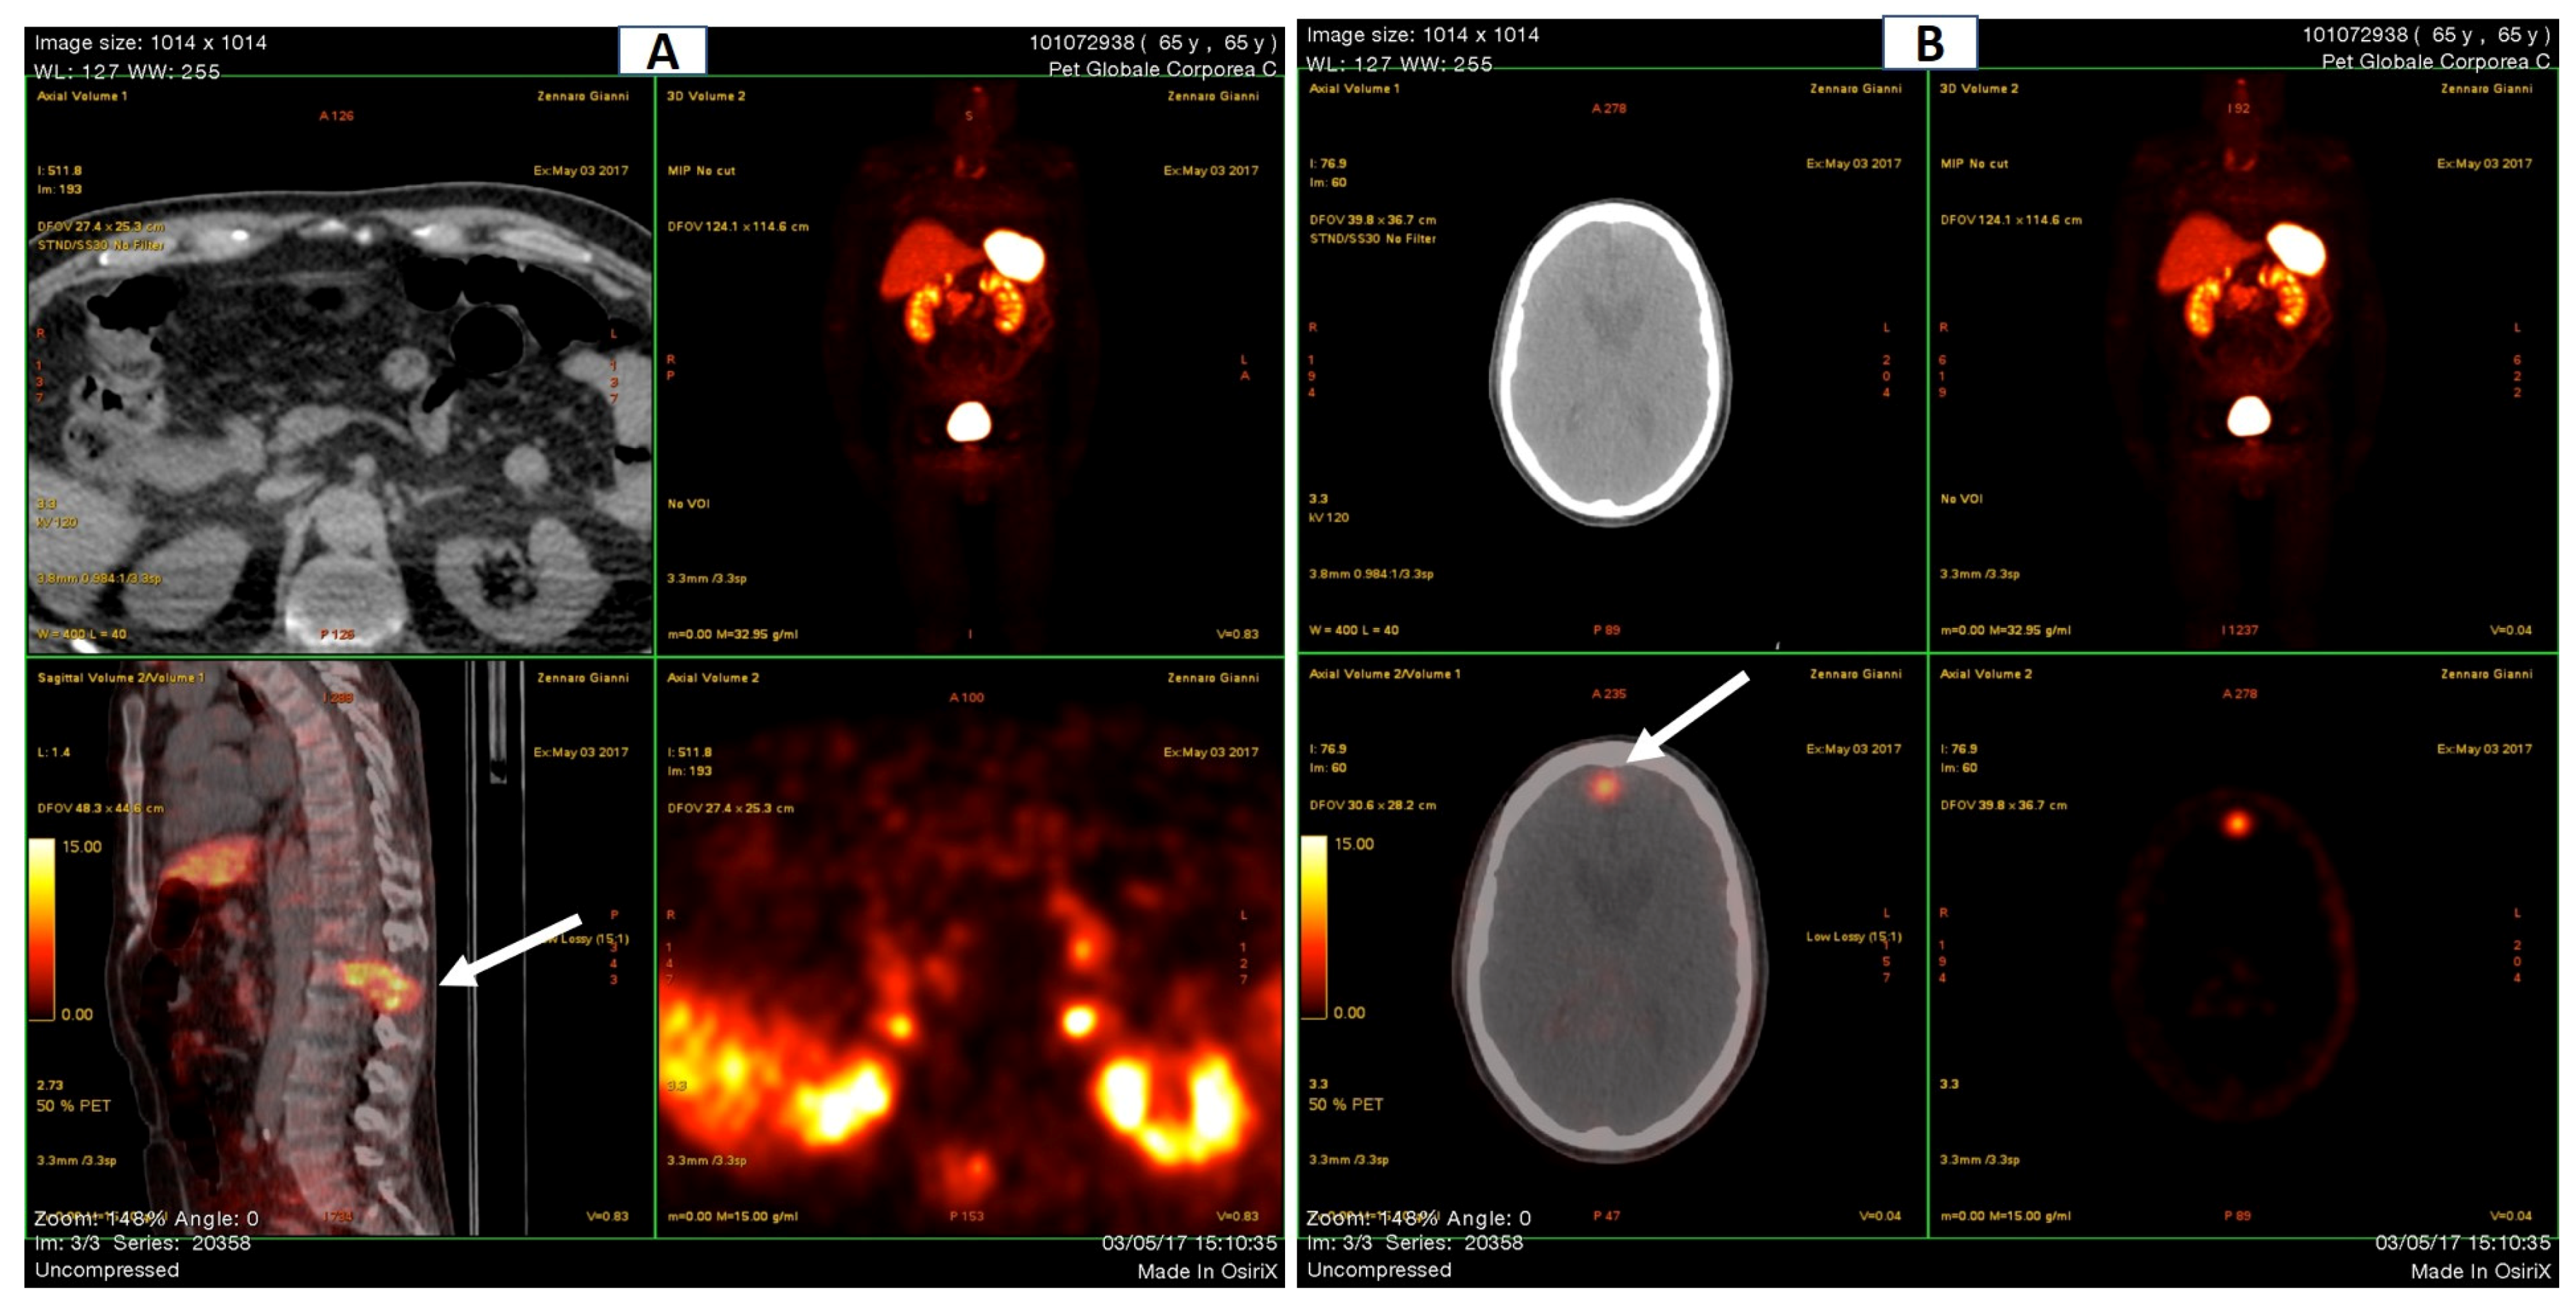

One year later, an MRI investigation showed an initial osteonecrotic area in the right knee and trabecular metaphyseal fractures of the distal femur and proximal tibia (Figure 2A,B), as well as healed distal tibial and ankle stress fractures (not shown).

Figure 2. Right knee MRI (July 2016). (A) Osteonecrotic area of about 2 cm in the external femoral condyle. (B) The arrows indicate femoral and tibial metaphyseal fractures.